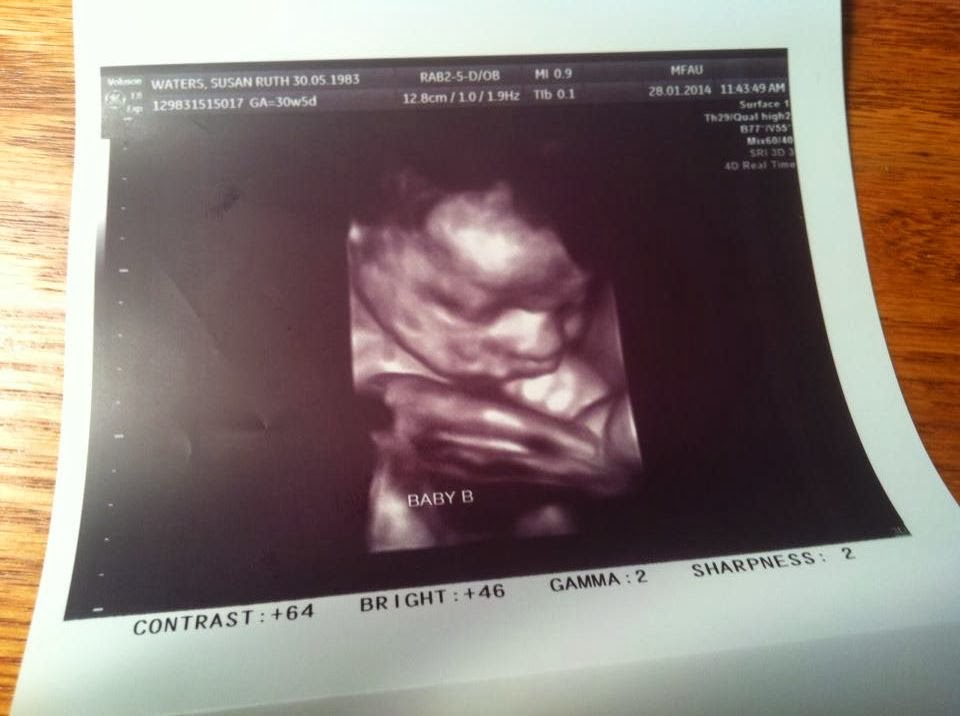

Look he’s sucking his thumb! Isn’t technology amazing to be able to capture this kind of stunning clarity? Susan had another ultrasound and here’s the baby boy…the baby girl is apparently not ready to have her photo so publicly displayed but they are both well.